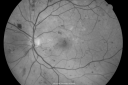

60-year old man has diabetic retinopathy in both eyes. His vision in the right eye is getting a little bit worse. He most recently had laser treatment in October of 2007 in both eyes.

VISUAL ACUITY: OD 20/60, OS 20/50. IOP: OD 16, OS 15. There is 2+ nuclear sclerosis in both eyes.

OD: Vertical C/D ratio is 0.1. There are patchy microaneurysms and laser to retinal hemorrhages. There are exudates and cotton wool spots.

OS: Vertical C/D ratio is 0.1. Similarly, there are microaneurysms and hemorrhage and laser.

OCT SCAN: The OCT scan shows central foveal thickness in the right eye of 338 microns, with significant parafoveal thickening. The left eye has parafoveal thickening with a normal foveal thickness.

Photos confirm clinical findings.

FLUORESCEIN ANGIOGRAM: FA shows multiple microaneurysms in both eyes.

1. BACKGROUND DIABETIC RETINOPATHY – LEFT EYE

2. MACULAR EDEMA, WORSE IN THE RIGHT EYE THAN THE LEFT EYE

DISCUSSION: I explained to the patient that the macula in the right eye is significantly more swollen than it has been in the past. I treated the right eye with focal laser. I asked him to return for a check in three or four months. I will re-evaluate both eyes and I may add a little laser to the left eye at that time.